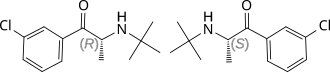

Selected image –

- The therapeutic index of a medication is a comparison of the amount that causes the therapeutic effect to the amount that causes toxic effects. Quantitatively, it is the ratio of the dose required to produce the desired therapeutic effect and the toxic dose. A commonly used measure of therapeutic index is the effective dose of a drug for 50% of the population (ED50) divided by the lethal dose for 50% of the population (LD50).

General images –